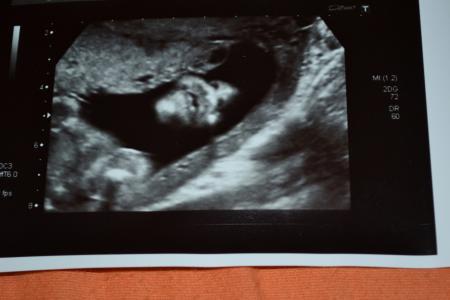

Hallo liebe mitkugelnden Zuerst war ich heute früh bei meiner Hausärztin und habe Urin abgegeben und es wurde ein Ultraschall der Nieren u.s.w gemacht weil ich immer wieder in letzter Zeit Schmerzen in der Blase bis zu den Nieren habe.Nieren waren o.k. aber der urin war nicht in Ordnung- Blasenentzündung,muß jetzt leider Antibiotika nehmen:-(. Um 11 hatte ich dann den Feindiagnostik Termin im KH. Der Arzt war super nett hat bei der Untersuchung alles genau erklärt.Meinte nur ich soll mir schon mal Laufschuhe besorgen,den mein Söhnchen war die ganze Zeit so am strampeln das er nie was zuende untersuchen konnte und immer von einem Organ zum anderen hüpfen mußte,was er halt gerade zu Gesicht gekriegt hatte.Er mußte den Kleine immerwieder anstupsen das er wieder die Position wechselt.Gut das ich vorher nochmal aufs Klo gegangen bin den der Druck war öfters unangenehm, naja hab ja wie gesagt auch noch die Blasenentzündung. Meine Mutter und mein Mann waren dabei und waren ganz faszieniert.Er hat letzt endlich doch alles ansehen können und es ist ALLES in Ordnung,so wie es sein soll.Sind ja so Happy. Haben auch ein paar schöne Bildchen mitbekommen,zwar keine 3d aber trotzdem schön. Lieben Gruß

Bild zu hatte heute Feindiagnostik:-) - Forum für September - Mamis